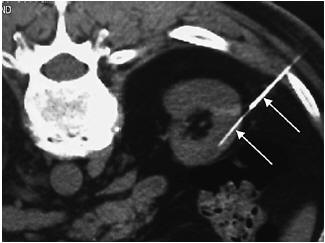

Figure 1. Response of eGFR (creatinine and cystatin C, 2012 CKD-EPI) to SRC injection. Although the overall group had a stabilization of the eGFR decline, 7 patients had a sustained increase of their eGFR. Day 0 represents the date of the first injection. Using linear mixed effects model, the annualized eGFR slope significantly improved from –4.63 ml/min per 1.73 m2 per year to –1.69 ml/min per 1.73 m2 per year (P = 0.015). CKD-EPI, Chronic Kidney Disease Epidemiology Collaboration; eGFR, estimated glomerular filtration rate; REACT, Renal Autologous Cell Therapy; SRC, selected renal cell.

and improved to -1.69 ml/min per 1.73 m2 per year (P = 0.015) postinjection (see Figure 1). Median follow-up was 24.3 (interquartile range 18.8, 27.7) months. Linear mixed effect model analyses (see Table 2) revealed that REACT slowed the increase of log parathyroid hormone (P = 0.04) and UACR (P = 0.001).